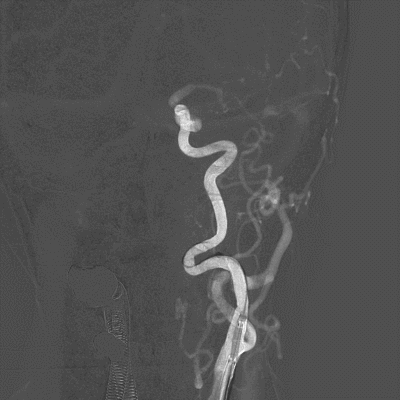

在Synchro14微导丝引导下将Gateway3.5-9mm球囊送至狭窄段,缓慢扩张球囊至6atm,撤除球囊压力后造影见狭窄改善。

撤出球囊导管,交换送入XT-27支架微导管至左侧大脑中动脉M1段,顺支架微导管送入Neuroform EZ 4.0-20mm支架,准确对位并释放支架。

造影见狭窄明显改善